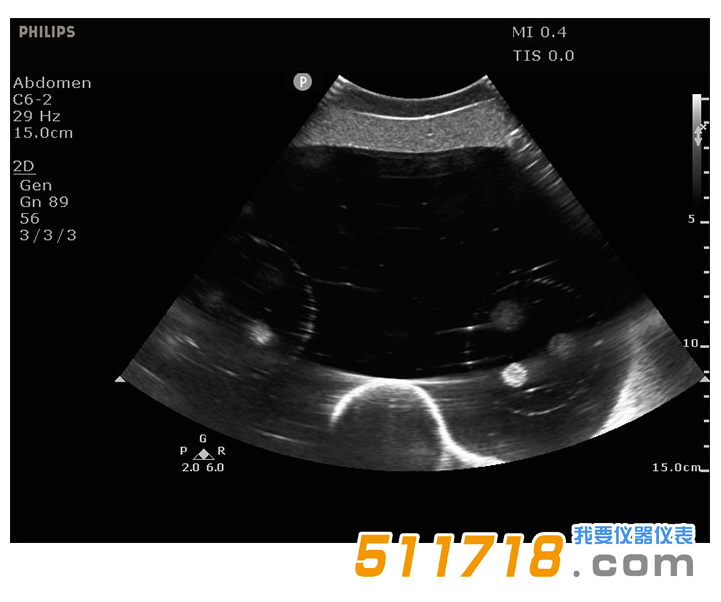

071B超聲圖像